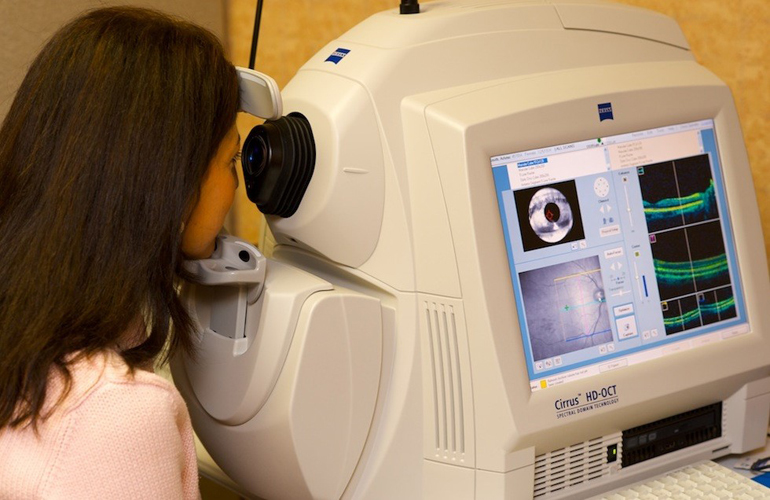

Диагностика зрения: Когерентная томография сетчатки